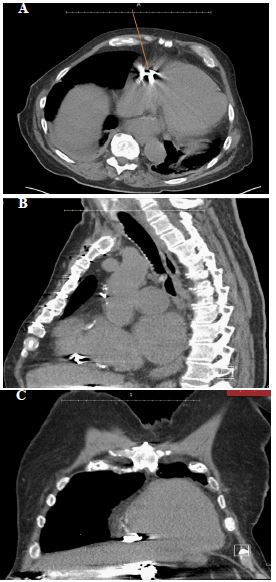

An 87-year-old man with an underlying history of coronary artery disease post coronary artery bypass graft, mitral valve replacement, moderate aortic stenosis, chronic right-sided heart failure, bronchial asthma, and atrial fibrillation initially presented with dyspnea and features of right heart strain on transthoracic echocardiogram. This was believed to be related to the development of intrahepatic porto-hepatic venous shunts from spontaneous portosystemic venous malformations, the largest of which was 4 centimeters. He had initially presented to the interventional radiology department for shunt embolization via coiling. The procedure was complicated by one of the coils migrating to the right ventricle. CT Thorax was performed to as sess the location of coil migration, and it revealed the coil to be deep in the anterior aspect of the right ventricle (Figure 1).

Figure 1: CT Thorax without contrast shows a coil embolized at the base of the right side of the heart before attempt of retrieval.